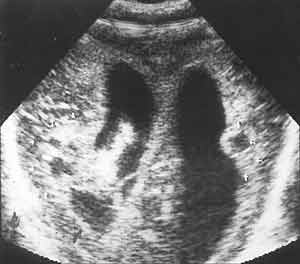

Ультразвуковая диагностика гнойных менингитов у детей первого года жизни.

Рис. 6. Стафилококковый менингит. Участки абсцедирования мозга (стрелки).